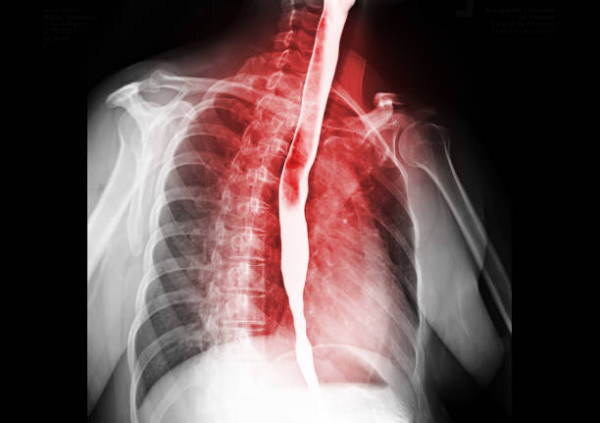

近日台灣花蓮門諾醫院腸胃內科主治醫生趙令瑞就分享了有關食道癌的資訊。食道癌初期沒有明顯症狀,患者較不容易在早期發現,隨癌症進入晚期後就會逐漸出現吞嚥困難及疼痛的症狀,甚至還會有食物逆流、心窩灼熱感、胸骨後或上腹部疼痛等情形。

趙令瑞醫生指出,食道癌的男性發生年齡中位數為 59 歲,約有 7 成個案集中發生於 50 至 70 歲的男士身上。食道癌最恐怖的地方在於「初期沒有明顯症狀」,患者極難在早期察覺。當癌症進入晚期,腫瘤開始阻塞食道,患者才會逐漸出現以下症狀,此時往往已錯過黃金治療期。

食道癌晚期可能出現吞嚥困難及疼痛、食物逆流、心窩灼熱感,以及胸骨後或上腹部疼痛等症狀。